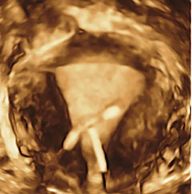

IUDs can irritate the endometrium, especially if not correctly positioned. Malpositioned IUDs are common

Endometrial polyps show as focal echogenic areas which obscure the normal central interface. A vascular pedicle, when present, helps to confirm a polyp.